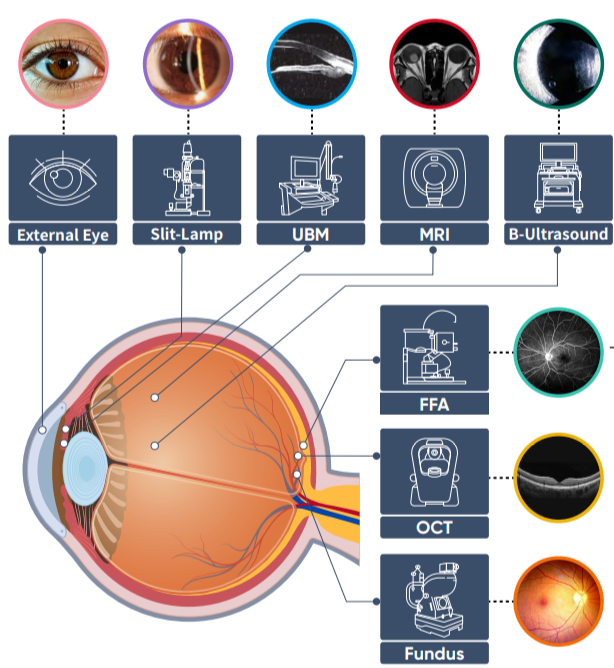

眼底成像技术

成像技术分为:

主要关注 5 个:

- 巩膜图 即(“白眼球”)External Eye

- 视网膜图像 fundus

- 裂隙灯图 Slit-Lamp

- 光学相干断层扫描(OCT)

- 光学相干断层造影(OCTA / FFA)

巩膜图 - 眼睛外部白色部分 即(“白眼球”):

裂隙灯图:

眼底图 fundus:

OCT 图:

OCTA:

分为 3 类:

-

从眼球前表面的详细检查(如裂隙灯摄影和巩膜图)

-

眼球内部结构的深入观察(如OCT和眼底图)

-

血管结构的详细分析(如OCTA)

裂隙灯图(Slit Lamp Photography):

- 用途: 裂隙灯是一种眼科设备,通过强光束来检查眼睛前部结构,如角膜、虹膜、晶状体和前房。

- 优点: 裂隙灯摄影对于发现和诊断角膜划伤、干眼症、白内障和青光眼等前段眼部疾病非常重要,并且能够记录治疗前后的变化。

巩膜图(Scleral Imaging):

- 用途: 巩膜图是显示眼球外部白色部分,即巩膜的图片。通常用来评估巩膜的健康状况,如检查巩膜的炎症、色素沉着或其他异常情况。

- 优点: 巩膜图可以帮助医生诊断和监测眼表疾病,如红眼病、巩膜炎症或结膜下出血等,也可用于评估眼外伤或手术后的恢复情况。

眼底图(Fundus Imaging):

- 用途: 眼底图是通过特殊的摄影技术捕捉眼球内部后部的图像,包括视网膜、视盘和黄斑等结构。

- 优点: 眼底图在诊断和管理诸如糖尿病视网膜病变、青光眼、视网膜脱落和年龄相关的黄斑变性等疾病中非常有用。

OCT (Optical Coherence Tomography):

- 用途:OCT是一种非侵入性成像测试,可以生成眼睛内部结构,特别是视网膜的高分辨率横截面图像。

- 优点:OCT对于检测视网膜疾病(如黄斑变性、黄斑水肿、视网膜裂孔)及其管理至关重要,因为它提供了细胞层级的结构细节。

OCTA (Optical Coherence Tomography Angiography):

- 用途:OCTA是OCT的一种进阶形式,能够以无需染色剂的方式展现眼睛内部的血流和血管结构。

- 优点:OCTA对于观察视网膜和脉络膜的血管病变非常有用,尤其是在诊断和监测糖尿病视网膜病变、视网膜静脉阻塞等疾病的血管变化。